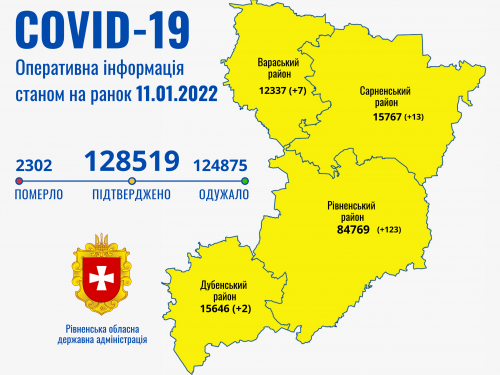

Коронавірус повертається: як стрімко зростає кількість хворих на Рівненщині (ВІДЕО)

Пів тисячі - у важкому стані, 9 жителів Рівненщини померли за добу від коронавірусу